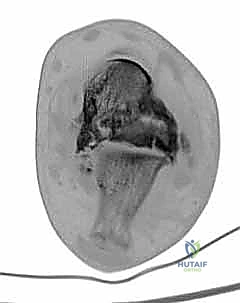

CT scan shows fatigue fractures through avascular talar body ( TECH FIG 7D,E ).

TECH FIG 7 • A. Patellar tendon bearing brace. B, C. Preoperative radiographs of patient with talar body avascular necrosis. D, E. CT scan of same patient in A . Note fatigue fractures in the talar body.